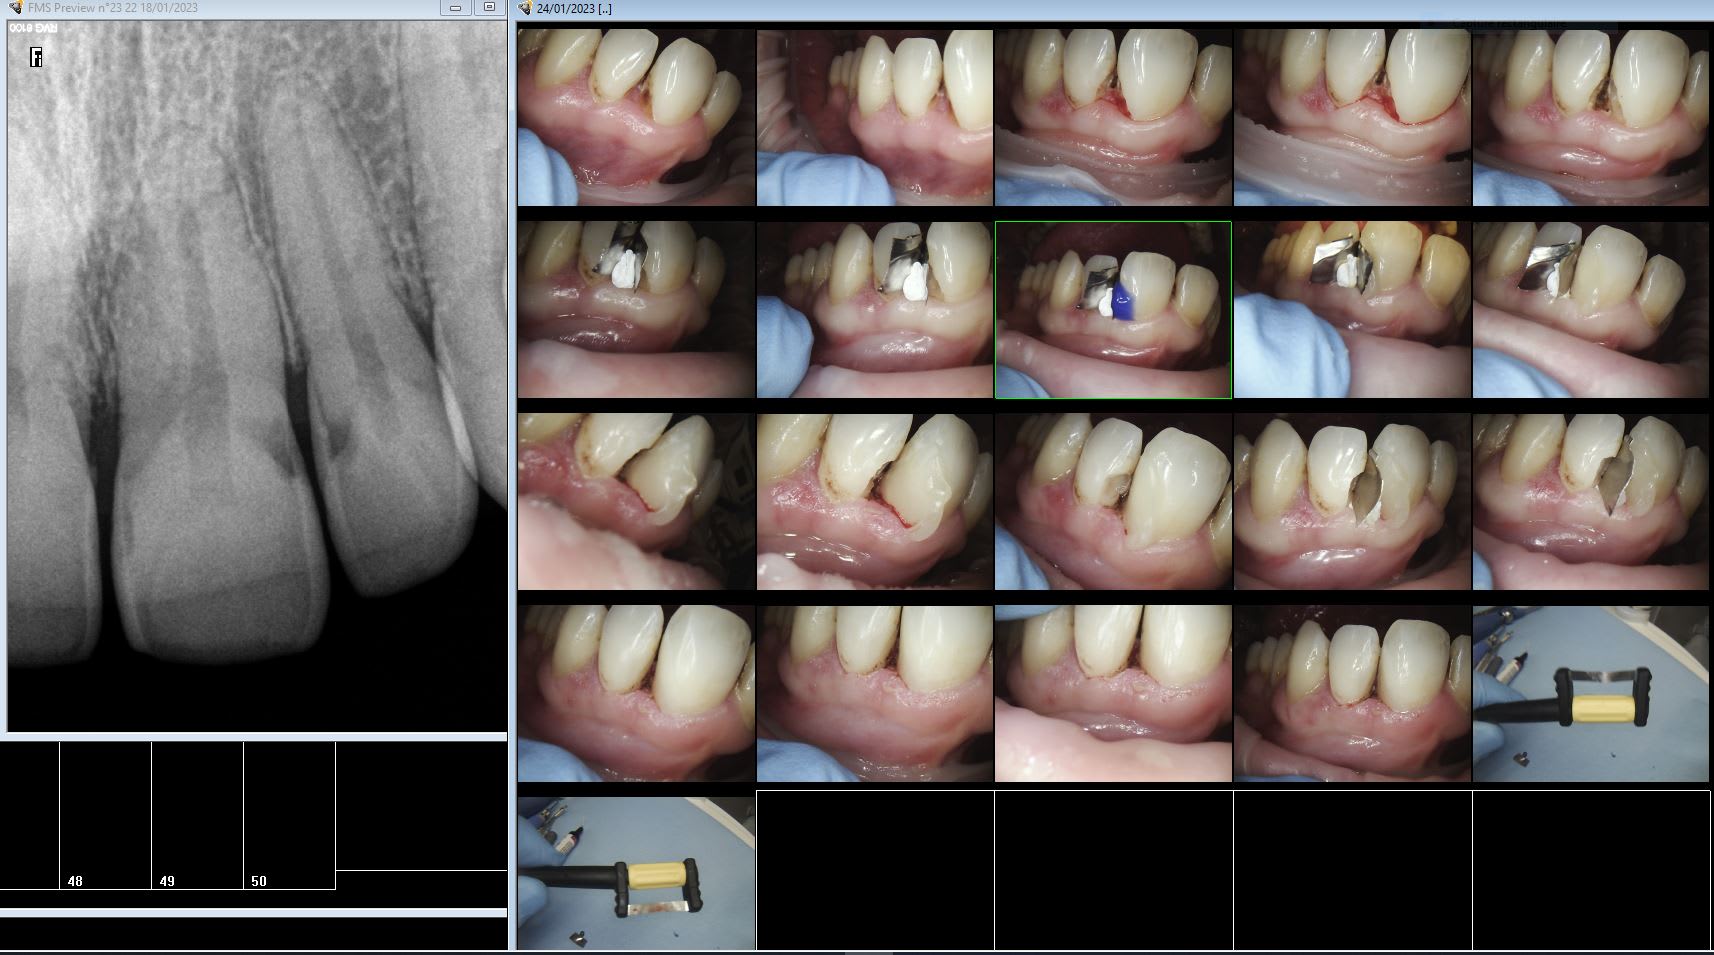

L'apothéose jack pot je prends ma retraite. -)